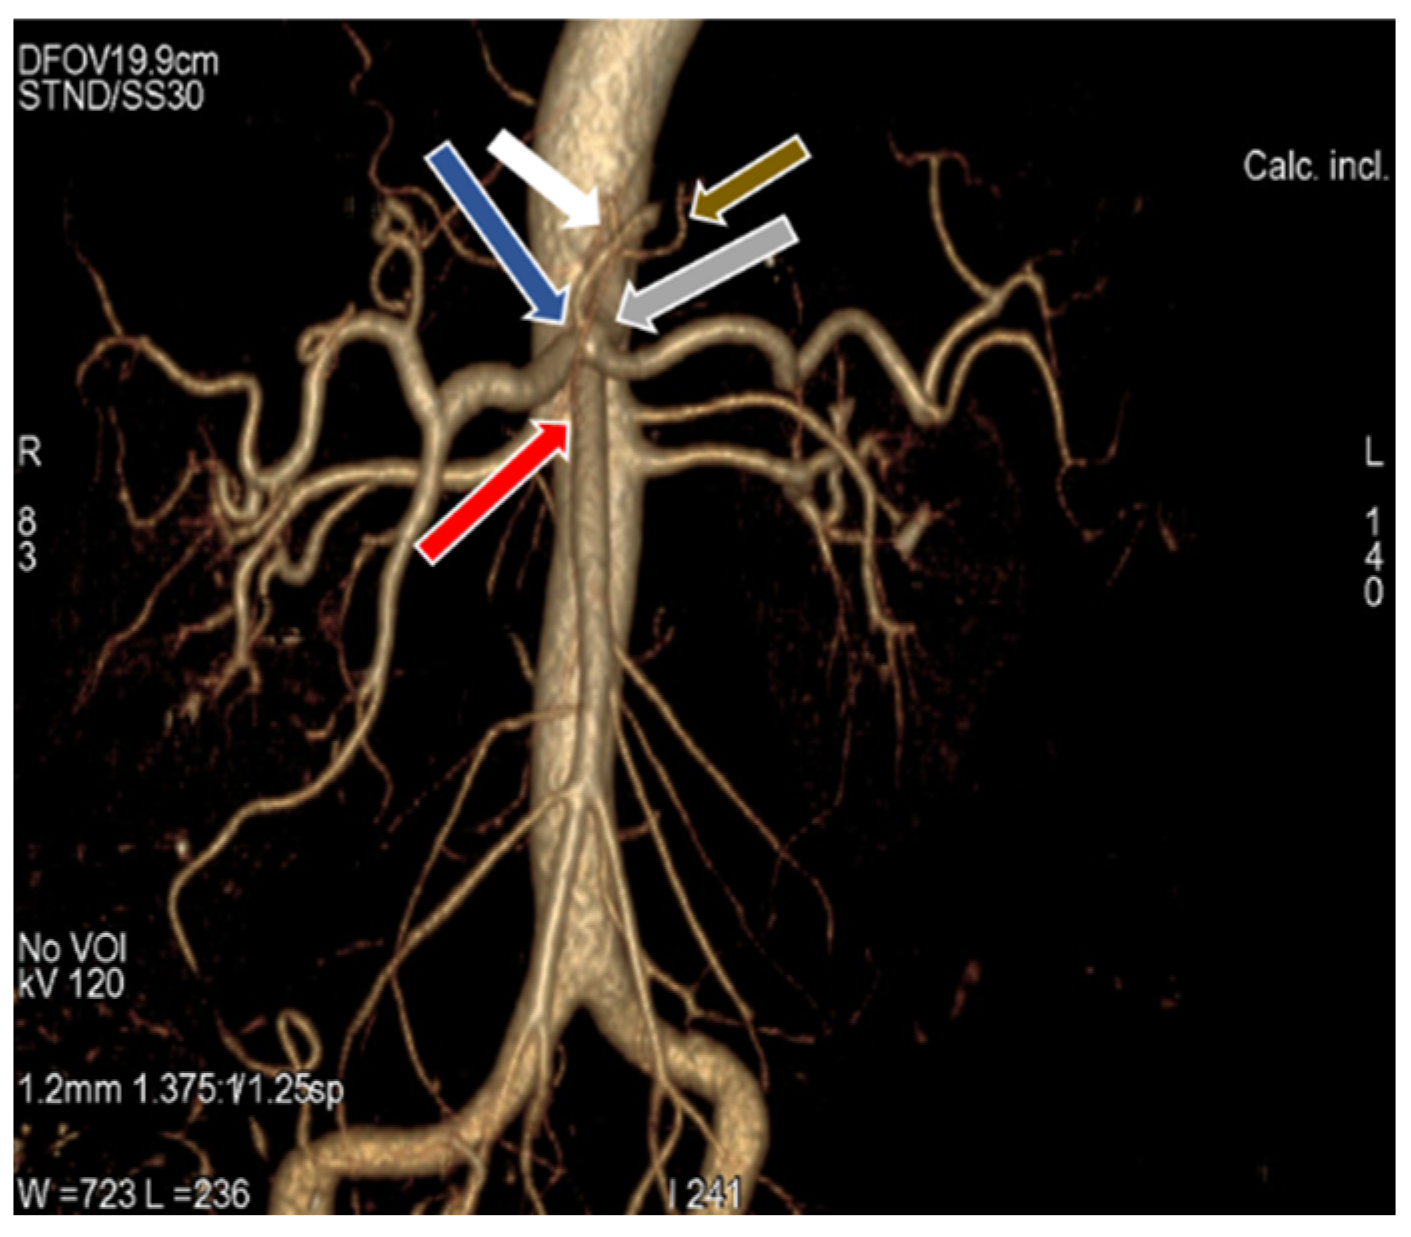

3.1. Variation in Origin and Branching Pattern of Celiac Trunk

3.2. Variation in Origin and Branching Pattern of Hepatic Artery